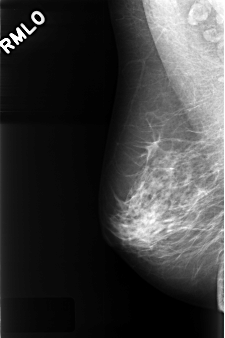

C_0325_1.RIGHT_MLO

RIGHT_CC LINES 4232 PIXELS_PER_LINE 2888 BITS_PER_PIXEL 12 RESOLUTION 50 NON_OVERLAY

RIGHT_MLO LINES 4392 PIXELS_PER_LINE 2920 BITS_PER_PIXEL 12 RESOLUTION 50 NON_OVERLAY